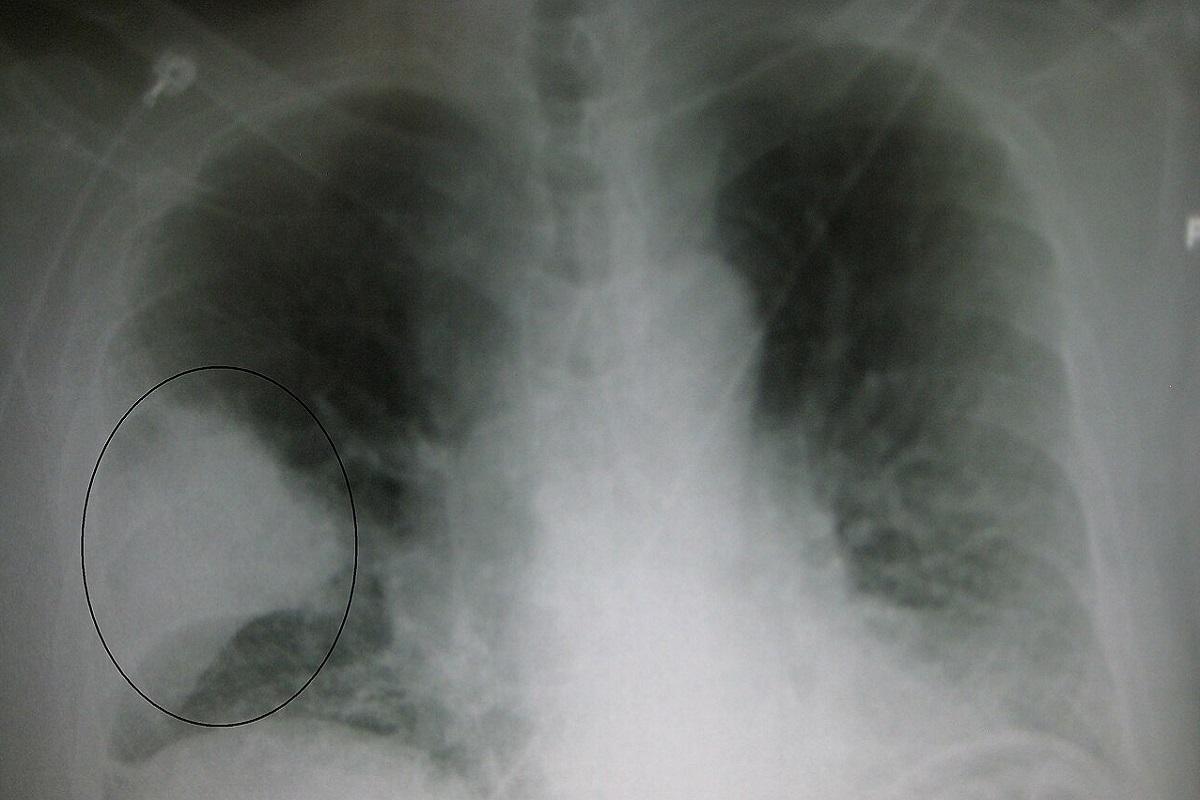

Hablamos de una infección grave, cuyo diagnóstico se realiza mediante una auscultación y la realización de una radiografía torácica. Y aunque existe tratamiento para curarla, los antibióticos, lo cierto es que se debe vigilar muy de cerca porque puede producir graves complicaciones como: